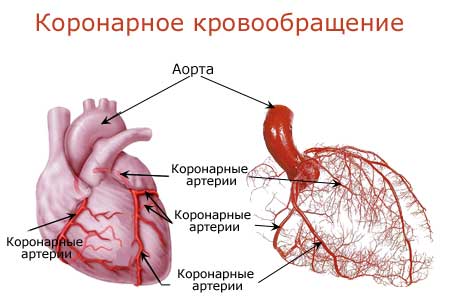

Анатомия коронарных артерий: КТ-изображения